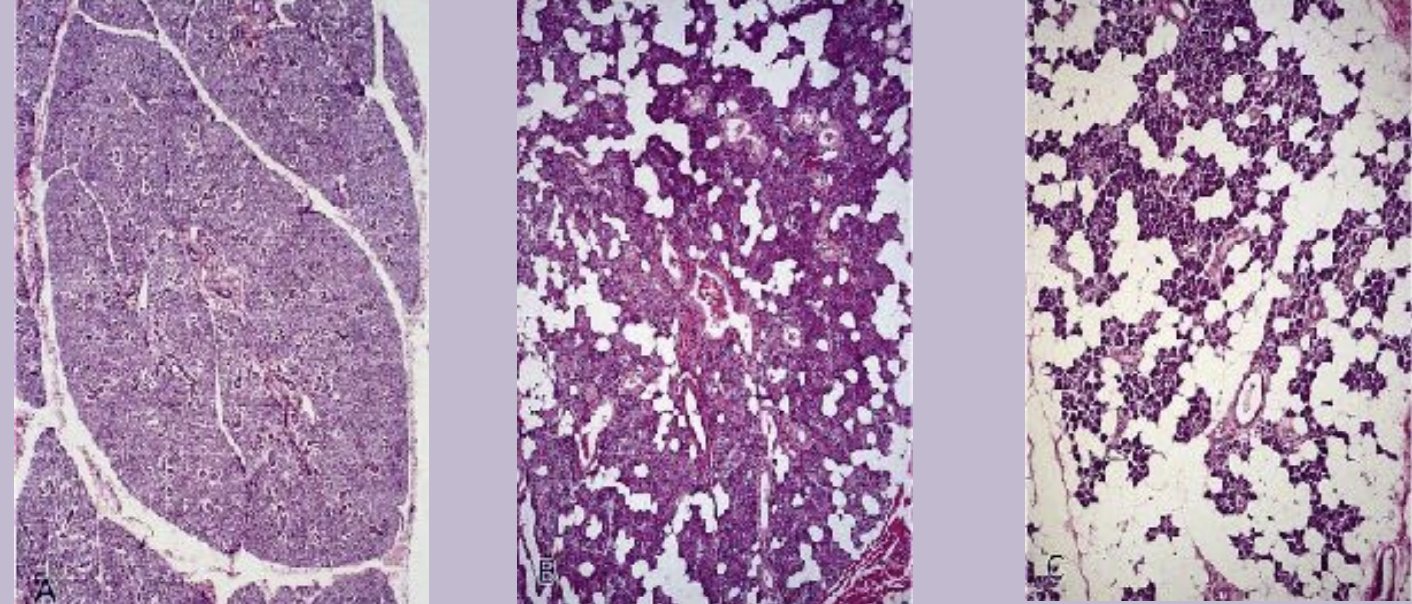

Salivary glands are essental organs of the oral cavity that produce saliva fluid. They are merocrine and exocrine glands producing saliva. They contain specialized epithelial cells called glandular epithelial cells.

Major salivary glands:

Parotid gland

Submandibular gland

Sublingual gland

Minor salivary glands are way smaller than the major salivary glands and are located in the submucosa. They are not found within gingiva and anterior part of the hard palate.

Structure of the salivary glands:

The functional unit of the salivary glands is acini (saliva).

Three types of salivary glands are: Serous, mucous, and seromucous (mixed)

Outer layer of connective tissue is Capsule , which serves to protect the underlying structures and provide support to the gland.

Septa are extentions of the capsule that extend inward, dividing the gland into smaller sections knows as lobes and lobules. this organization helps to compartmentalise the gland, providing a structured layout

Age changes in salivary glands include :

fibrosis and fatty degenerative changes

presence of oncocytes (eosinophilic cells containing many mitochondria)